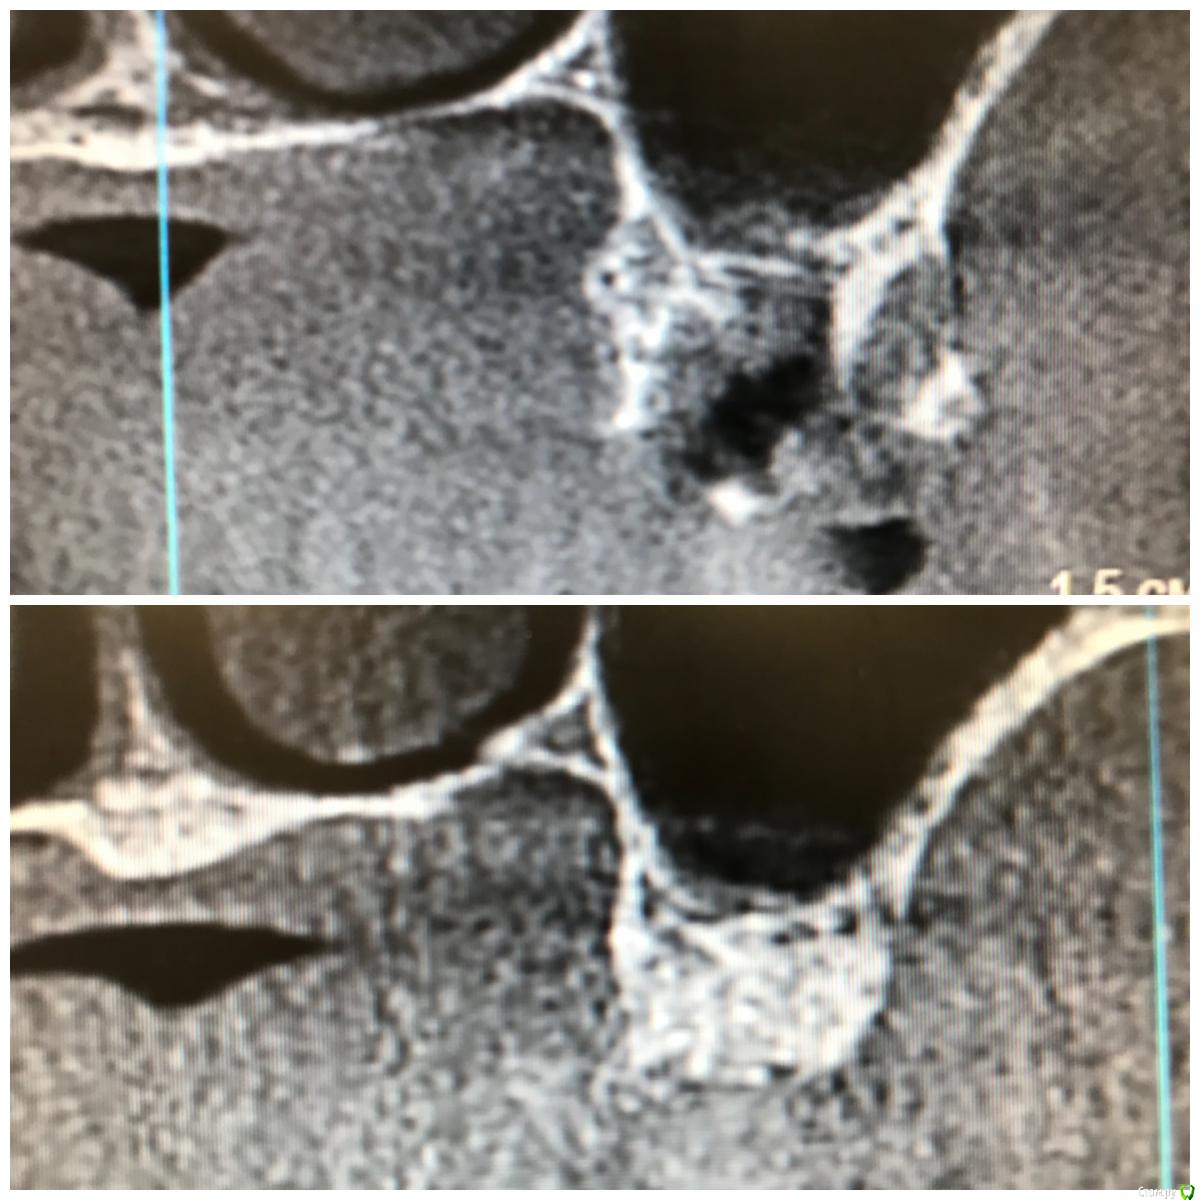

колесников Опубликовано 5 декабря, 2017 Поделиться Опубликовано 5 декабря, 2017 Пациентка N обратилась с жалобами на «выбухание дёсны» в обл 24. На клкт однотогенные кисты в/ч и значительные деформации гребня. От имплантации в перспективе категорически отказалась,потому было решено провести лишь подготовку гребня под чсп ( хотя было желание сделать открытый синус в обл 16/26 доступом через кистозную полость). Удаление причинных зубов без откидывания лоскута,вылущивание и кюретаж. Дефекты заполнены кортикальным аллографтом Sureoss,перекрыто бугром на ножке и vip ст. Был сдан чсп. Повторный визит через 7 мес. На клкт коегде кистозный свод просел. Видимо не достаточно графта было оставлено. Гребень выраженный,широкий. Случай показательный в плане эффективности и стабильности консервации лунки,очевидно что чсп не оказывает деформирующкно влияния на аугментированый гребень. По поводу удалить и подождать или удалить,заполнить и подождать,еще Carlos отмечал ,что кистозное выбухание в пазуху надо использовать для получения объема в зоне предстоящей имплантации. PS.Неудачи встречаются. Они связаны с нарушением герметизма лунки: некроз лоскута,распад сгустка и инфицирование графта. У меня было 2 жестокие неудачи,в первом случае пациент активный курильщик,второй любитель коньяка. В обоих случаях дополнительно применялся A-PRF ,но даже он не смог противостоять такому деструктивному влиянию агрессивных сред. 3 Ссылка на комментарий